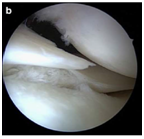

正常的半月板

损伤的半月板